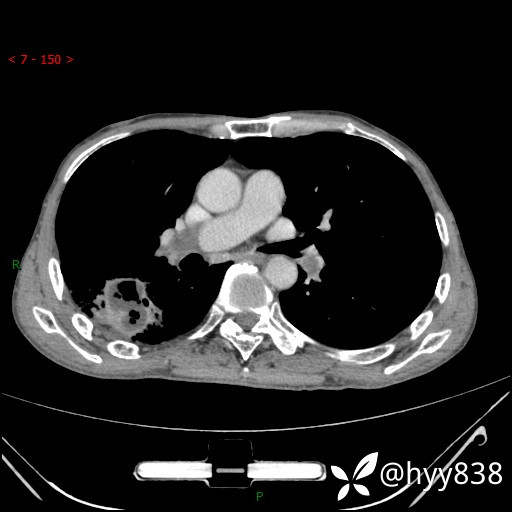

静脉期